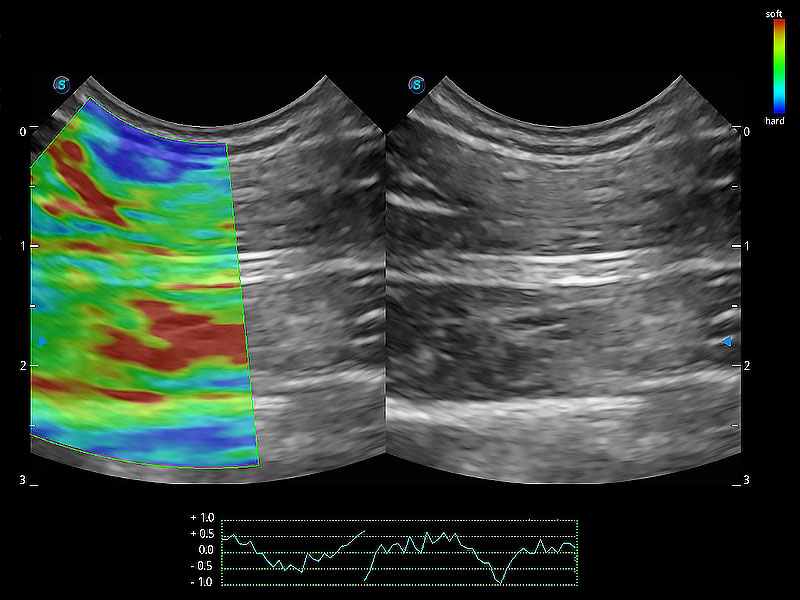

操作簡(jiǎn)便,無需高頻度外力作用即可真實(shí)反映組織的形變,快速評(píng)估腫瘤良惡性。